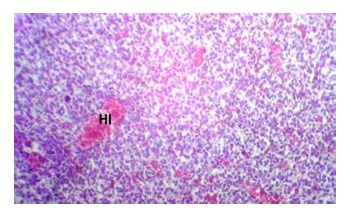

Effect of Vitamin E Against Atrazine-Induced Fetal Liver Damage in Adult Wistar Rats